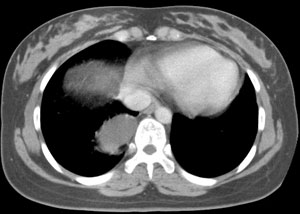

女,22岁,无明显症状

强化

后纵隔食管右侧可见一囊性病灶,密度均匀,边缘光滑,未见钙化,与食管关系密切。无明显强化。

考虑食管囊肿。

鉴别:1、支气管囊肿,多位于气管或气管分叉前后。

2、神经源性肿瘤,实质性肿块,可压迫、侵蚀邻近骨质。

首先定位在肺内。肿块最大径在右下肺叶后基底段,胸椎椎体右边偏后部。与气管、食管无关,如果是支气管或食管囊肿应该有细蒂与之连接。肿块边缘光整、密度均匀一致、轻度均匀强化。右主支气管轻度受压,右肺含气量降低,右胸腔略萎陷。

手术证实 支气管囊肿

自己分析一下误诊的原因,如果不对,请老师们指正:该肿瘤位于支气管分叉处,附着于右主支气管后外壁。因为病灶逐渐长大和重力的关系,呈水滴状下垂,故造成其最大径不在纵隔内的假象。轻度强化也是没有仔细和平扫对比给自己造成的假象。才疏学浅,没有仔细分析病例,也没有仔细体会各位老师的不同意见,草率之至,羞愧!